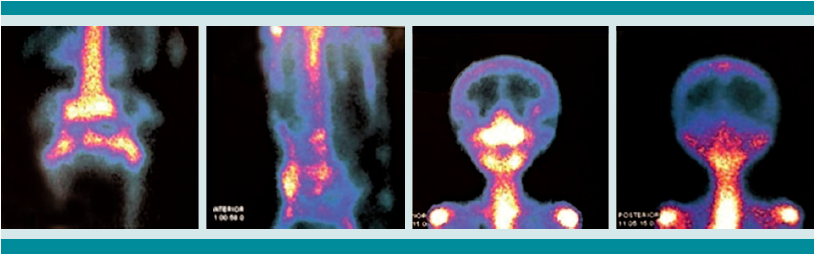

Estudios de imagen

La tomografía axial computada de alta resolución puede demostrar lesiones de la primoinfección o linfadenopatía, aun cuando la radiografía de tórax se reporte normal.13 La resonancia magnética se utiliza en mayor medida para la tuberculosis músculo esquelética y de tejidos blandos y, como en este caso, para diferenciar una tumoración de un granuloma en la columna vertebral.14 Otros métodos, como la gammagrafía, que con marcadores como Tecnecio 99 tiene una especificidad de 30% y con galio de 70%. El SPECT y PET tienen mejor especificidad que la tomografía o gammagrafía para discernir entre tuberculosis y lesiones cancerosas,15 con un valor predictivo negativo mayor de 90%, a diferencia de pacientes con tuberculosis pulmonar, además de mayor captación e identificación de lesiones óseas se puede utilizar como auxiliar en tuberculosis extrapulmonar. Finalmente, pueden ser de gran ayuda para determinar el grado de actividad de la enfermedad y la respuesta al tratamiento indicado.